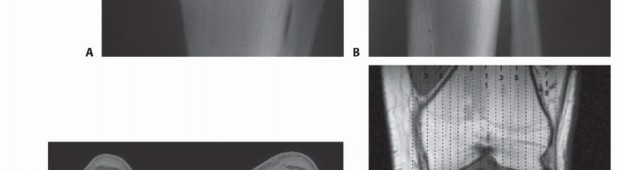

التصوير المقطعي المحوسب والتصوير بالرنين المغناطيسي

يُعد التصوير المقطعي المحوسب (CT) والتصوير بالرنين المغناطيسي (MR) أدوات لا غنى عنها لتحديد مدى تدمير القشرة العظمية، والامتدادات داخل النخاع العظمي، وامتدادات الورم في الأنسجة الرخوة المحيطة. هذه البيانات حيوية لتحديد مستوى استئصال قصبة الساق، والذي يكون عادةً 3 إلى 5 سم بعيداً عن منطقة إصابة الورم داخل النخاع.

يمكن للتصوير بالرنين المغناطيسي أيضاً الكشف عن "الآفات القافزة" (skip lesions)، وهي بؤر ورمية منفصلة عن الورم الرئيسي، والتي قد تؤثر على مدى استئصال قصبة الساق. يوفر الأستاذ الدكتور محمد هطيف تحليلاً دقيقاً لهذه الصور لضمان تحديد هامش جراحي آمن وفعال.

صورة مقطعية توضح الورم الذي يملأ مشاش قصبة الساق القريبة.

صورة مقطعية أخرى للورم في قصبة الساق.

صورة بالرنين المغناطيسي تظهر مدى امتداد الورم داخل النخاع العظمي.

صورة مقطعية توضح تدميراً قشرياً وامتداداً للأنسجة الرخوة للورم.